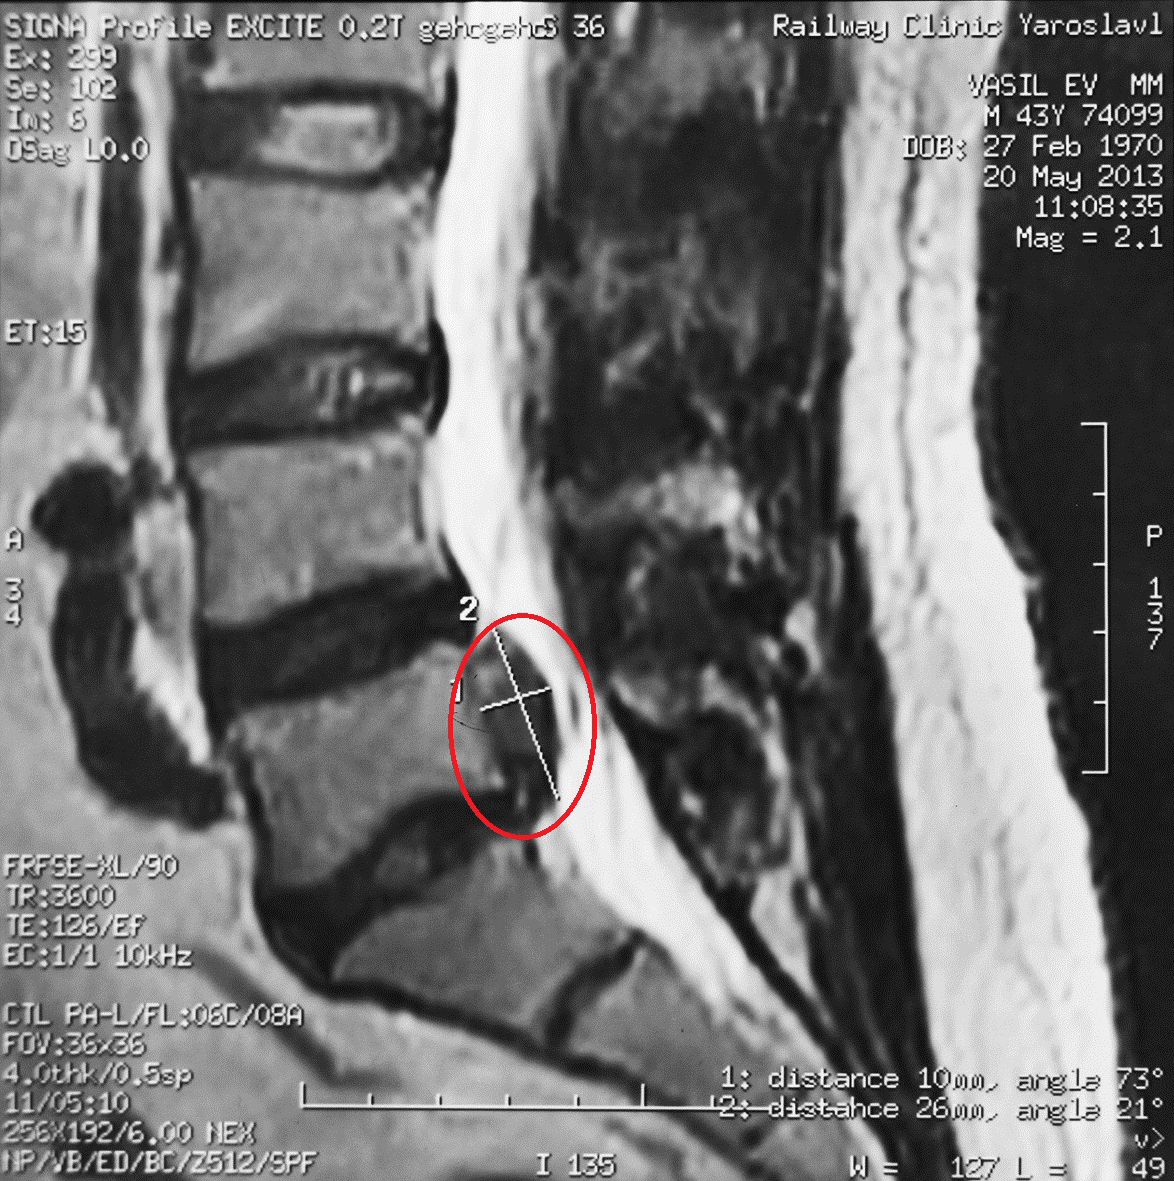

Секвестрации грыжи диска что это

Секвестрации грыжи диска что это 105 фото